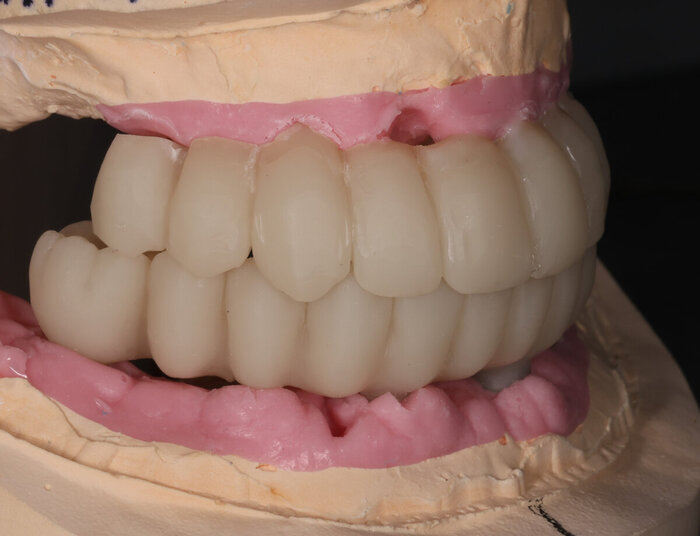

Вот как выглядит цифровая принтованная постановка:

Цифровая принтованная постановка

Разница - в первом варианте зубы не из стандартного набора, а те, что пациенту подходят больше. С этим прототипом можно даже пожить какое-то время, попривыкать к нему. Понять, что нравится, а что не особо.